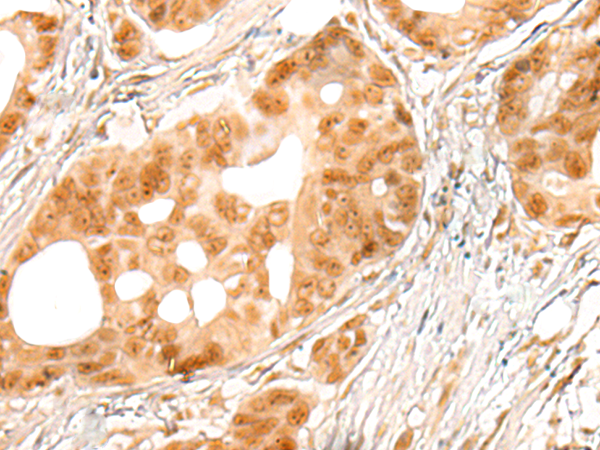

Applications: |

ELISA, IHC |

IHC positive control: |

Human colorectal cancer and Human gastric cancer |

IHC Recommend dilution: |

25-100 |